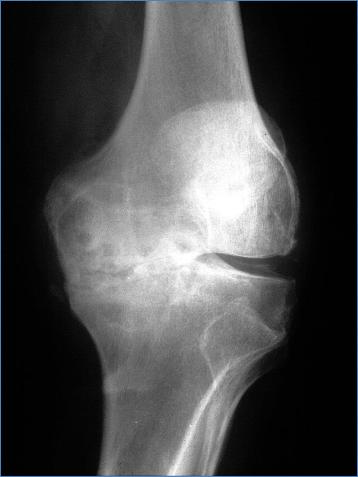

Пример деформирующего артроза коленного сустава.

Резкое сужение внутренней части суставной щели свидетельствует о полном разрушении там суставного хряща. Видны субхондральный склероз и кистозная дегенерация под суставными поверхностями.